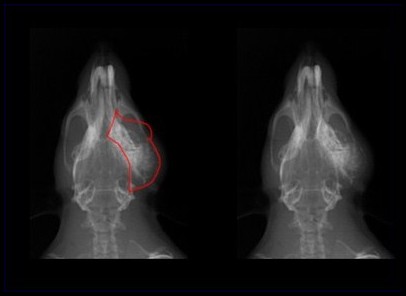

Tumeurs de la Glande de Zymbal chez Rattounette

Radiographie du même type de tumeur chez un rat différent